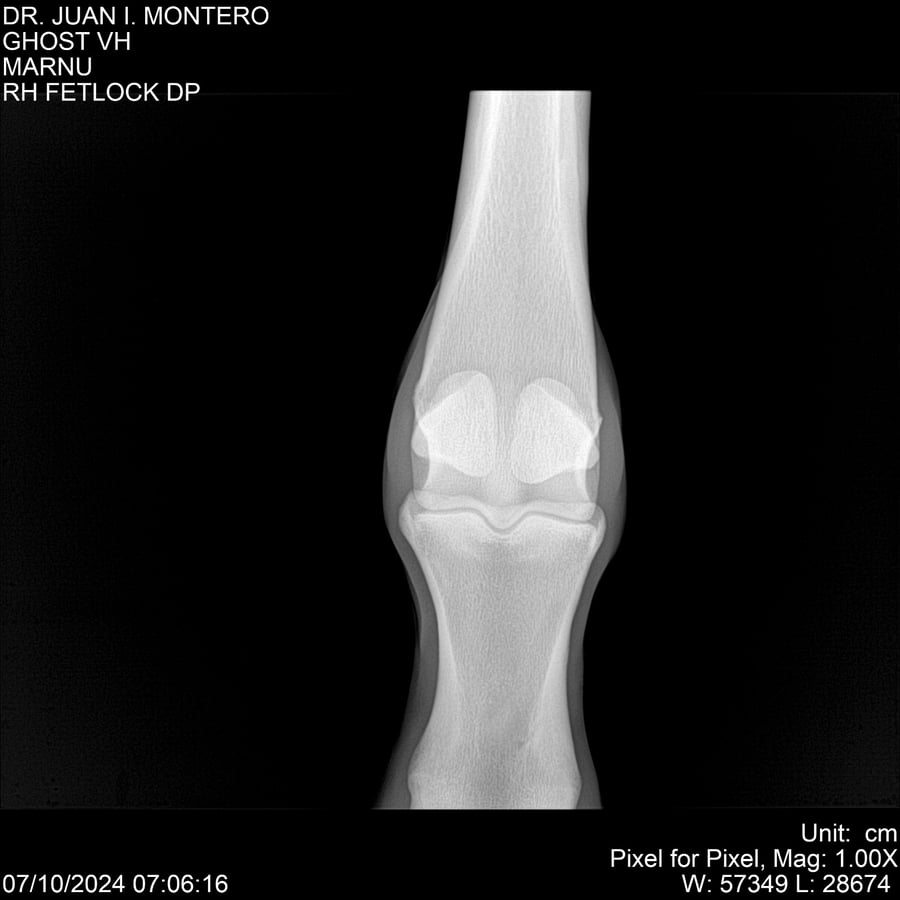

LOTE 15, GHOST VH 🔥 🔥 🔥 Lote Anterior Volver al remate Lote Siguiente Ficha Contacto Montevideo - Ficha del Lote Identificador: #282525 Categoría: Yeguarizos Montevideo - 69 Visualizaciones ClicData Contacto Empresa: Abelenda N. R., Walter Hugo Nombre*: Teléfono* : E-mail* : Mensaje Enviar Registrese gratis Este contenido Exclusivo está disponible sólo para usuarios registrados Ingresar